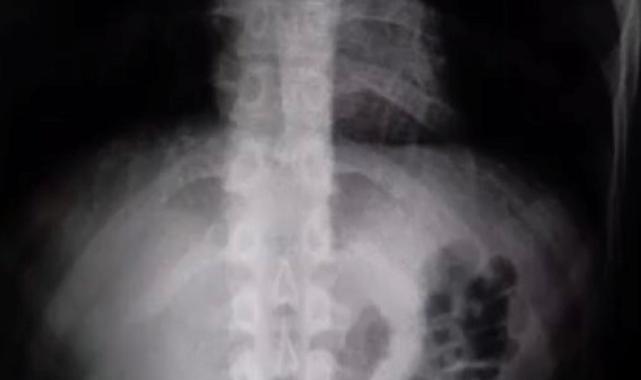

Gözaltına alınan şüphelinin hastanedeki iç beden muayenesinde 77 adet kapsül şeklinde 1 kilo 134 gram narkotik madde ele geçirildi.

Şüphelinin midesindeki maddeler cerrahi müdahale ile çıkarılırken hakkında uyuşturucu madde ticareti yapmak suçundan adli işlem başlatıldı.